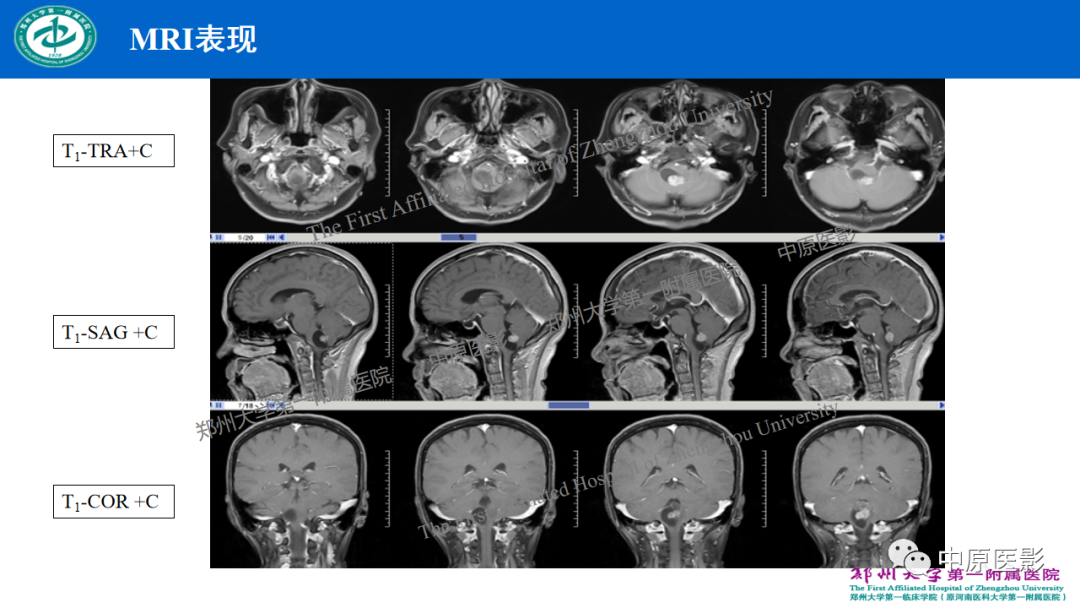

【病例】枕骨大孔区脉络丛乳头状瘤1例MR影像-4